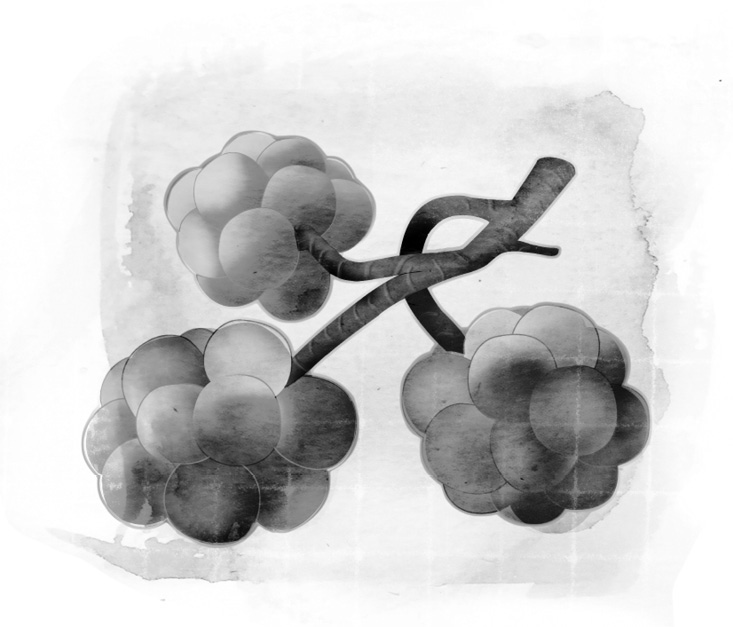

◆支气管

支气管是深入肺脏的主要通道,空气会从喉头进入支气管。支气管有两个分支,空气可以进入左边的支气管,也可以进入右边的。

支气管一再分叉开来,如同一棵树的树枝一样。越接近肺脏的支气管分叉得越细小,最终变成细支气管。接着,这些通道变形成微小的气囊,称为肺泡,肺泡便是空气和二氧化碳进行交换的地方。

说起来,空气交换的过程其实并不需要费力。空气从外界被送进肺脏之后,它顺着气管往下流动,进入肺脏里面的支气管。先前曾经说过,这些管子一再分叉成细小的通道,称为细支气管。细支气管里面有成排的纤毛,那是毛发般的微小细胞,会随着呼吸而活动,帮助肺脏排出黏液。细支气管的终点是形状有如气球的微小气囊,称为肺泡。人体拥有超过三亿个肺泡,包覆在微血管所形成的网子里面,这便是氧气和二氧化碳进行交换的地方。

肺泡会随着呼吸的进行而膨胀、收缩。我们吸入的空气含有氧气,氧气在肺泡扩散开来,穿透肺泡壁和邻近的微血管,进入红血球里面。血液吸收了氧气之后,流出肺脏,接着再流向心脏。心脏的搏动把富含氧气的血液输送到全身上下,于是氧气被携带到各个器官、各个组织的每一个细胞。细胞把氧气用掉之后,会制造出二氧化碳,这是细胞氧化的副产品。血液会把二氧化碳吸收回去,送到肺脏,吐出体外。